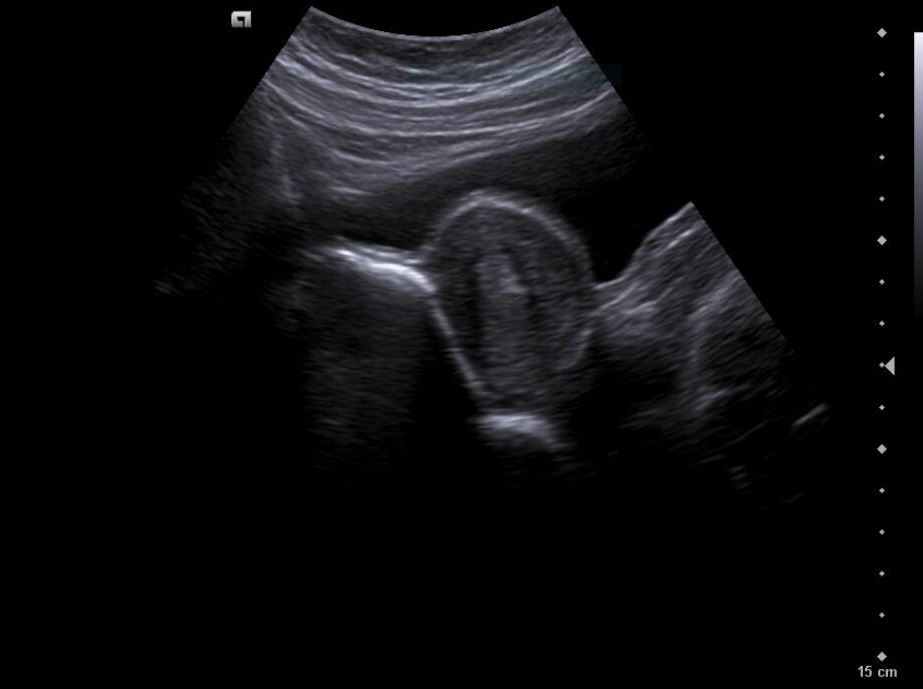

• Revisión ginecológica incidental muestra una imagen heterogénea en anexos: masa de aspecto solidoquístico en ovario derecho (43 × 33 mm), con zona hiperecoica y posible componente quístico. Se plantea teratoma como primera hipótesis diagnóstica.

Diagnóstico inicial: Teratoma ovárico derecho versus cuerpo lúteo hemorrágico.

• Formación sólidoquística en anexo derecho de 43 × 33 mm con signos sugestivos de teratoma.

• Lesión quística densa adyacente de 6 mm (endometriosis o componente adicional del teratoma).